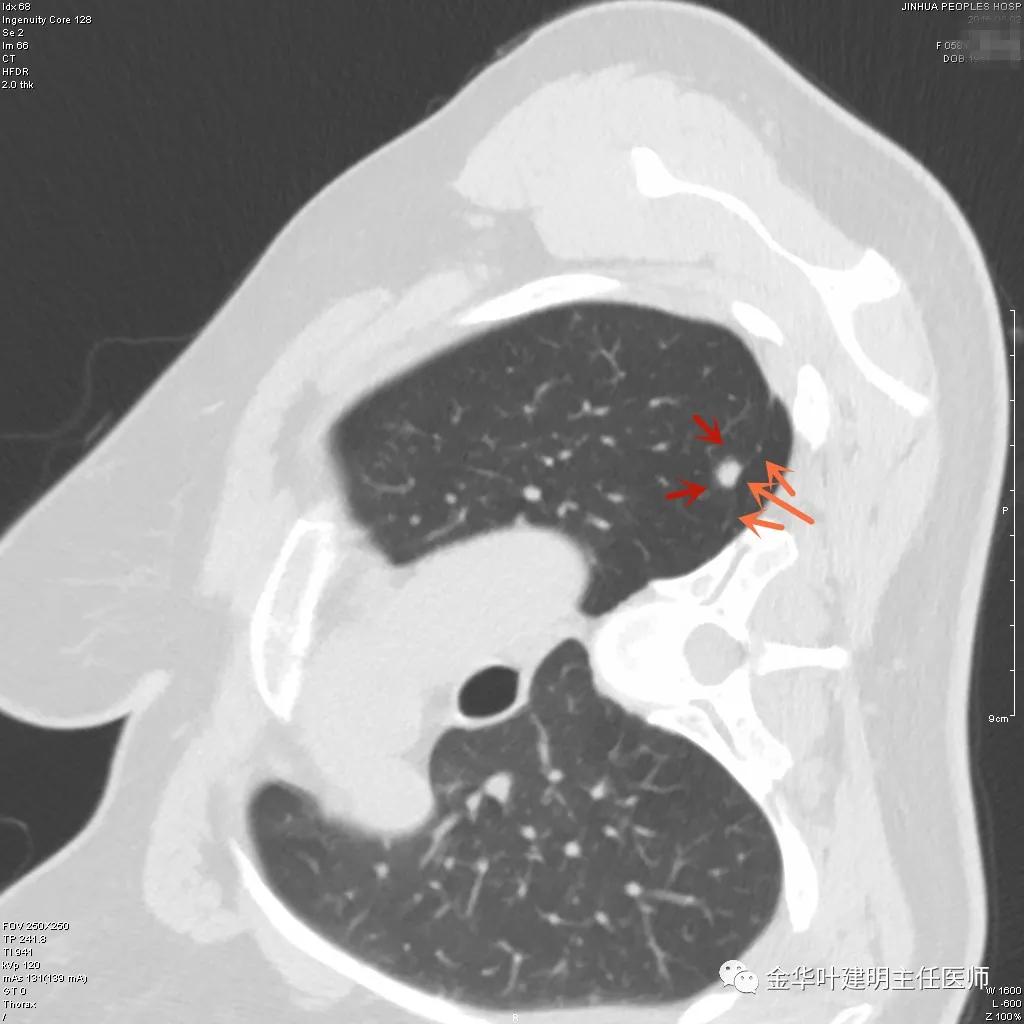

上图是肺内淋巴结。但我们看有明显血管进入病灶,胸膜似有牵拉,恶性的特征也不少。